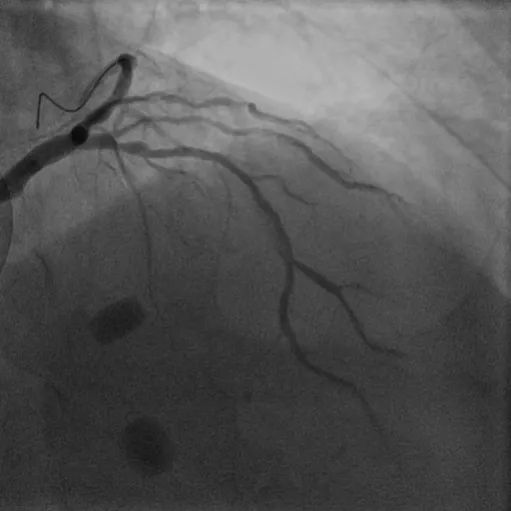

病例3

LM-LAD钙化病变:患者73岁女性,主因胸痛2小时入院,既往高血压病史,诊断不稳定型心绞痛。该患者1周前因心绞痛入院,CAG显示RCA95%狭窄伴血栓,于RCA植入一枚支架。患者左主干严重钙化病变狭窄80%,合并LAD弥漫钙化最重处狭窄90%,精准充分预处理格为重要,姚朱华主任团队综合评估患者病情后决定择期IVUS指导下行Shockwave冲击波球囊治疗。IVUS检查显示LM-LAD弥漫性钙化,最重处360°环形钙化,应用3.5*12mm Shockwave冲击波球囊顺利到达病变处,自LAD中段至LM末端连续释放脉冲,在左主干处释放4个周期(40个脉冲),成功于LM-LAD植入3枚支架,术后IVUS评估达到理想的支架膨胀及贴壁效果。

术前冠脉造影

植入支架后